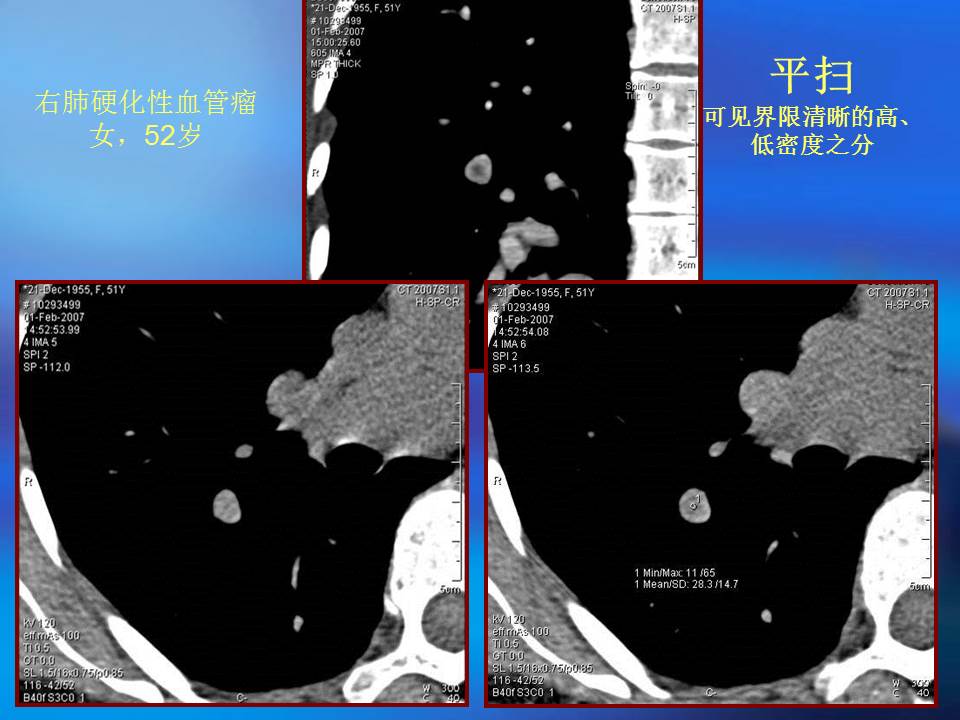

肺良性肿瘤